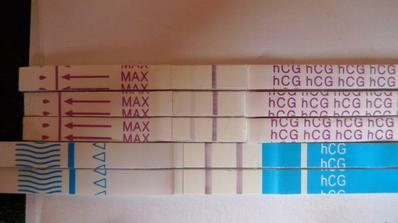

V březnu 2010 jsme se začali snažit o sourozence pro Ondráška. Zadařilo se hned druhý měsíc a já jsem někdy v polovině května našla na těhu testíku druhou čárku. Ze začátku jen "ducha", ale postupem času čárka krásně sílila. Máme oba dva s manželem velikou radost. Včera (12.8.2010) jsme byli na velkém ultrazvuku v 19. týdnu...miminko je v pořádku, má všechno co mít má a dokonce už víme, že Ondrášek bude mít sestřičku.